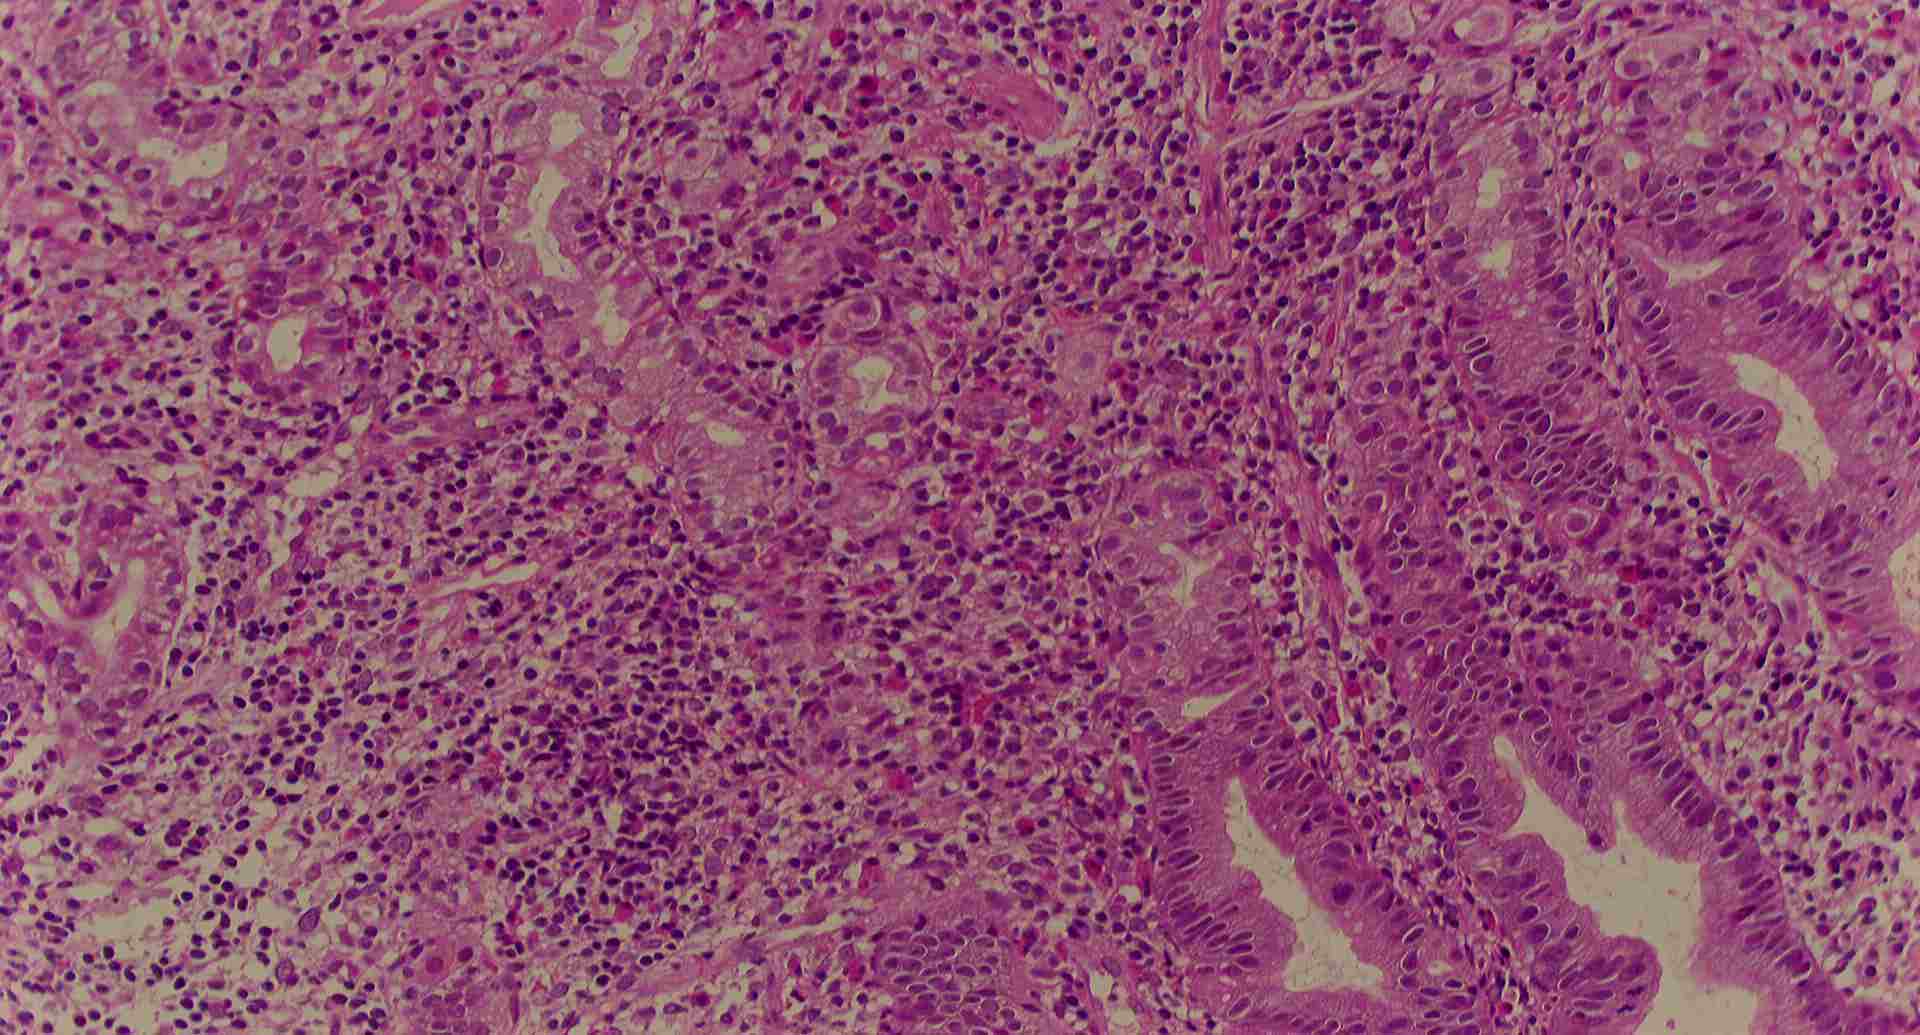

標本13